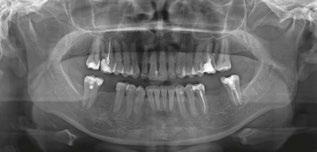

A visual screening tool validation study has recently been concluded and submitted to the Journal of Evidence-Based Dental Practice. This study is the collaboration of this author and the principal investigator Judith Owens, MD, funded by a grant from the American Academy of Craniofacial Pain (AACP). This study looked at the risk factors for pediatric sleep-disordered breathing (SDB) and craniofacial features, validated using the PSQ and a 22-item parent reported measure for SDB risk in children. Subject characteristics included age, sex, race, and ethnicity. Various craniofacial features were evaluated, such as: retrognathic mandible, open mouth posture, convex profile, midface deficiency, flat cheeks, concave profile, dolichocephalic face, frontal asymmetry, forward head posture, and rolled shoulders. It also included intraoral evaluation of: crowding of teeth, crossbite, narrow vaulted palate, crowding of upper teeth, narrow

palate, open bite, tongue thrust, crowding of lower teeth, narrow lower jaw, tongue tie, and “heart”-shaped tip of tongue. Twelve data collection sites across the U.S. were sourced to demonstrate ease of use, reproducibility, and which conditions had highest correlation. It was found that the following conditions had the highest correlation in decreasing order: forward head posture, narrow vaulted palate, open bite, tongue thrust, tongue tie, and heart-shaped tongue.

Figure 1: The validated Pediatric Sleep Questionnaire is the most utilized screening tool

Figure 2: BEARS Sleep Screening Tool